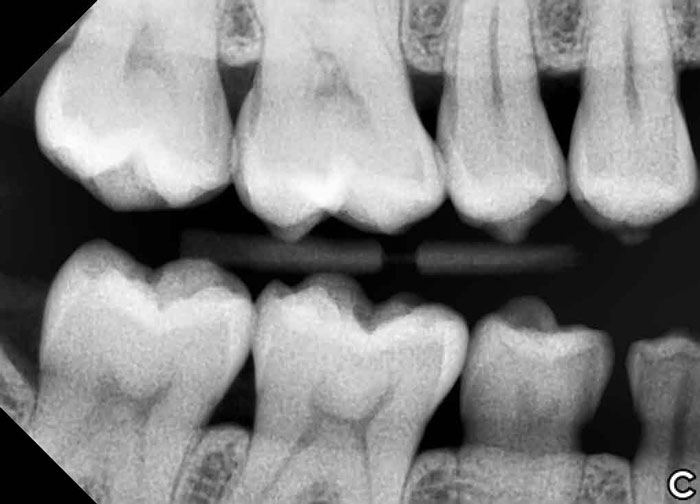

DIGITAL X-RAYS

Digital x-rays offer improved imaging with less radiation to our patients than conventional x-rays. Digital x-rays have wider range of viewing options to catch problems earlier. Early detection usually means more conservative treatment and consequently better oral health. Being able to educate and explain problems with visual aid is a tremendous benefit to the patient and doctor alike.